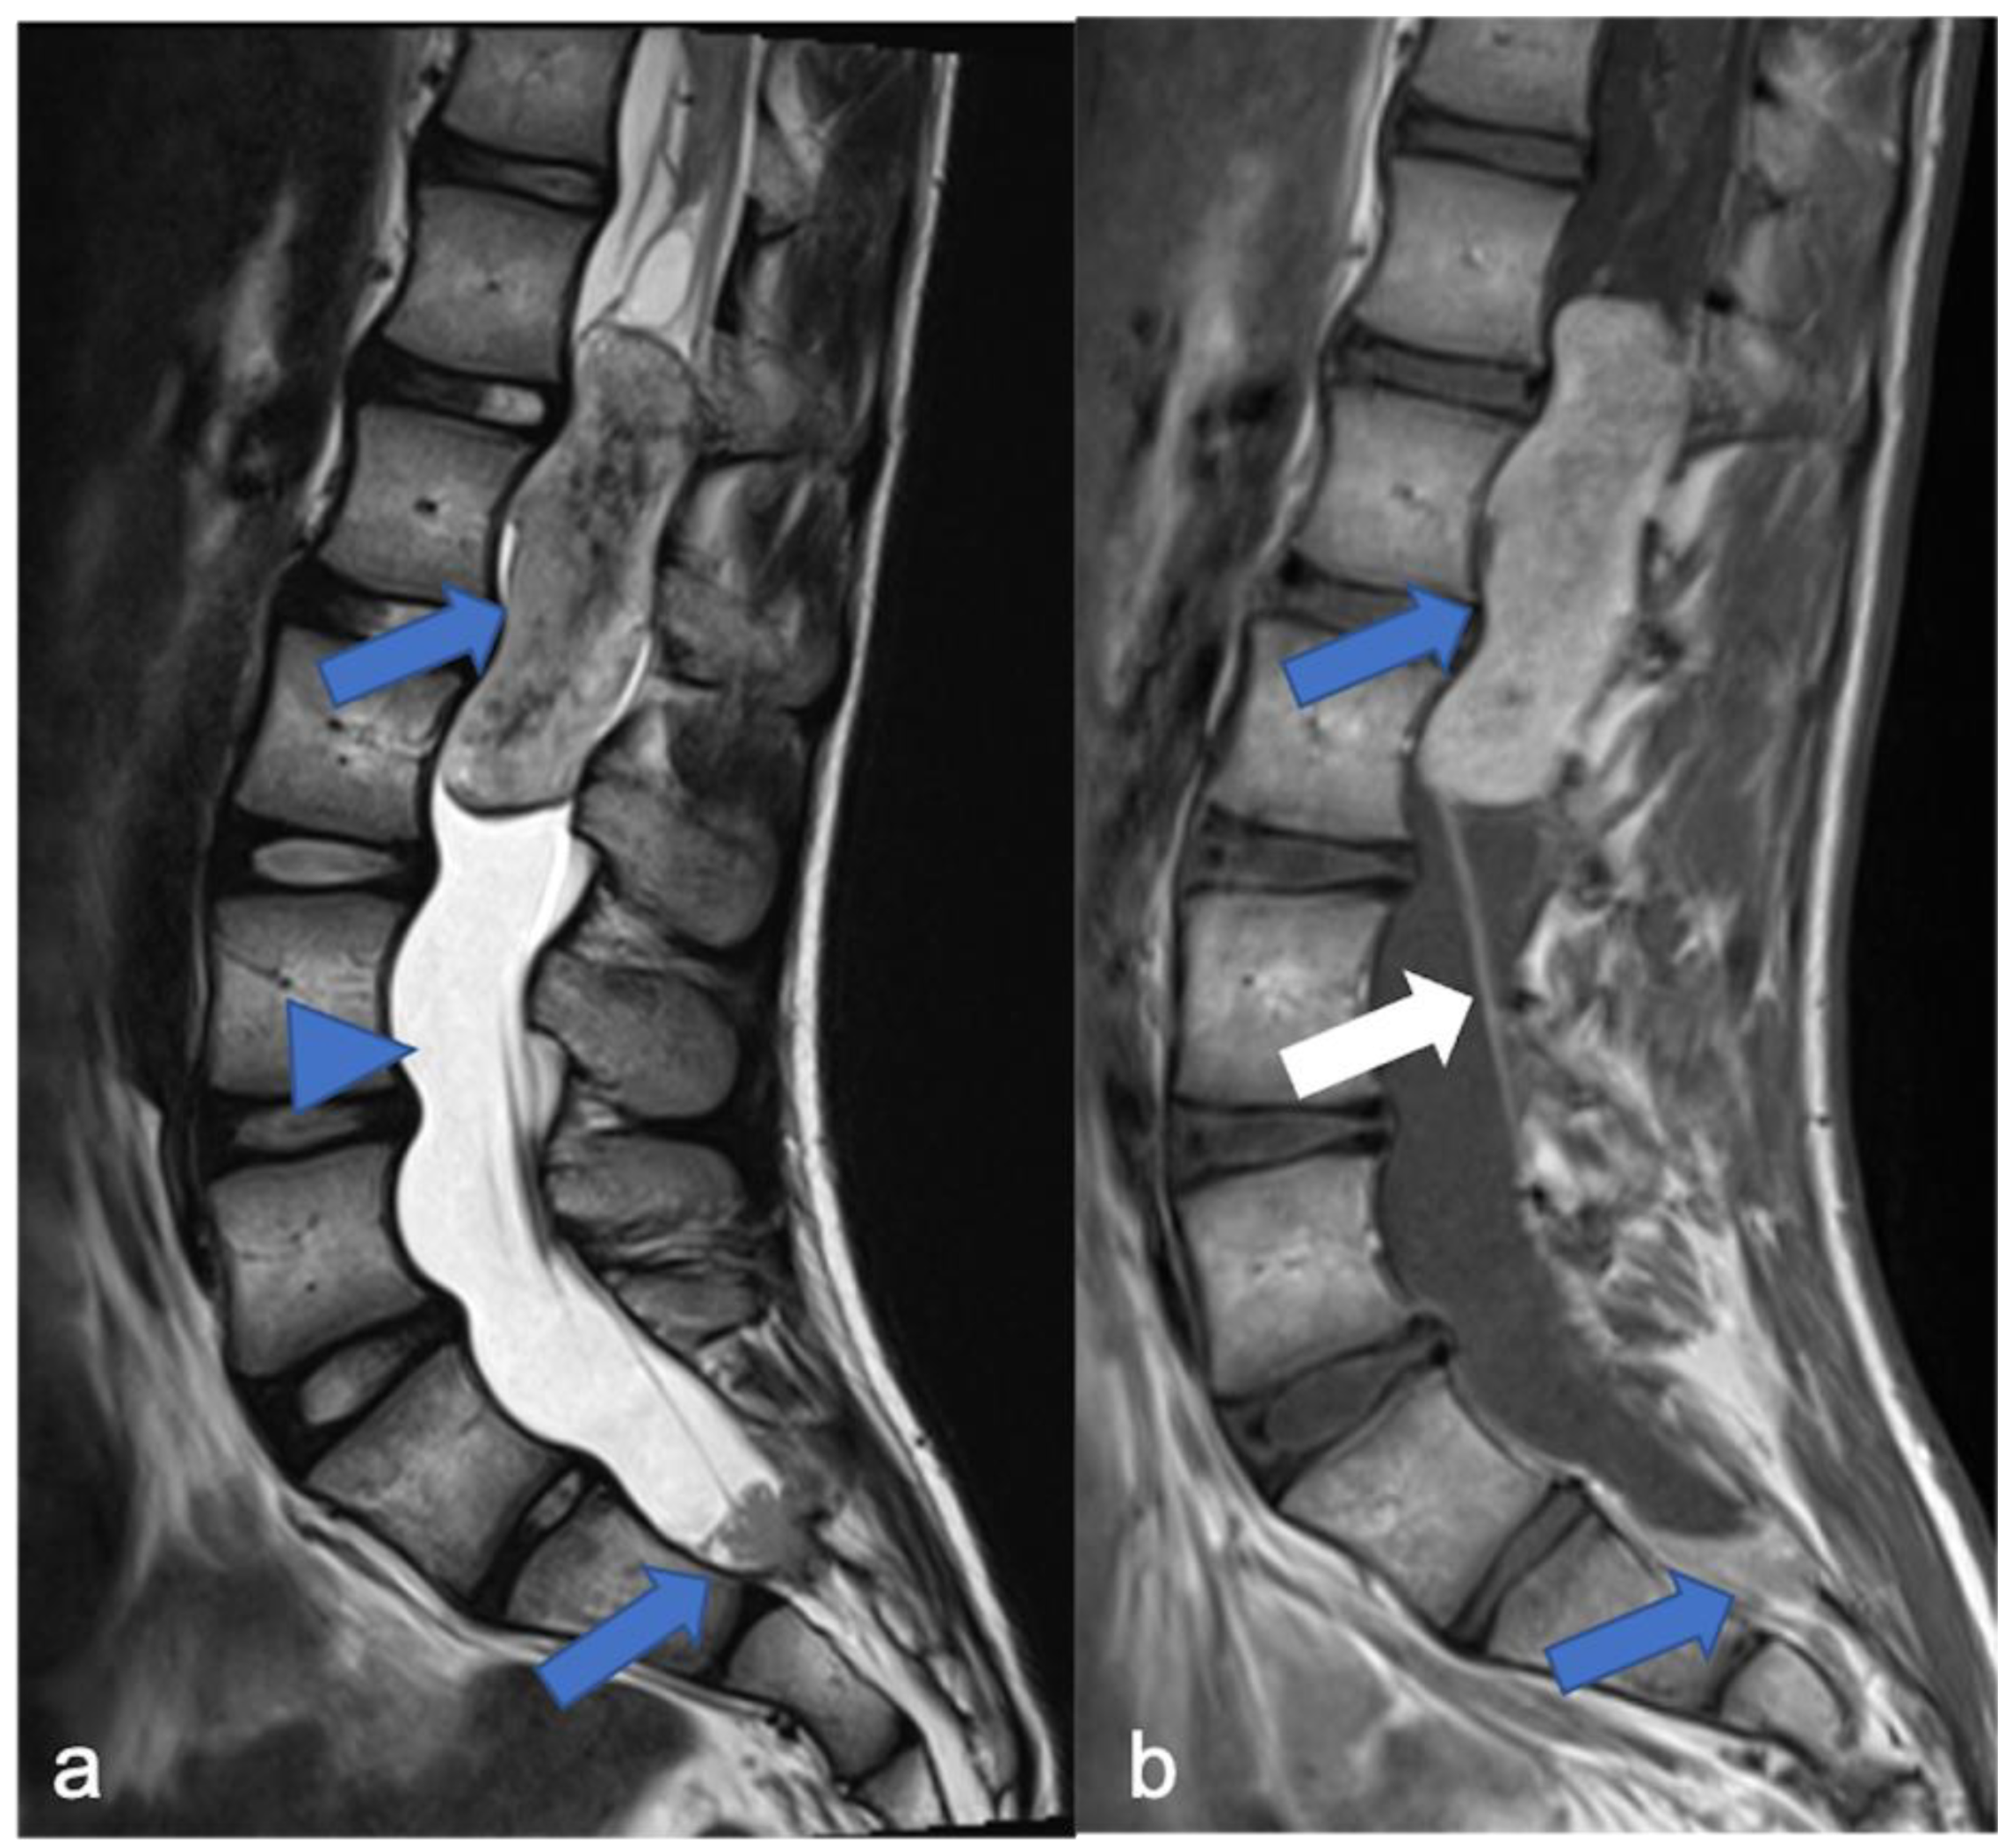

3. Ependymomas

- Ghasemi, D.R.; Sill, M.; Okonechnikov, K.; Korshunov, A.; Yip, S.; Schutz, P.W.; Scheie, D.; Kruse, A.; Harter, P.N.; Kastelan, M.; et al. MYCN amplification drives an aggressive form of spinal ependymoma. Acta Neuropathol. 2019, 138, 1075–1089. [Google Scholar] [CrossRef]

- Swanson, A.A.; Raghunathan, A.; Jenkins, R.B.; Messing-Jünger, M.; Pietsch, T.; Clarke, M.J.; Kaufmann, T.J.; Giannini, C. Spinal Cord ependymomas with MYCN amplification show aggressive clinical behavior. J. Neuropathol. Exp. Neurol. 2019, 78, 791–797. [Google Scholar] [CrossRef]

- Wippold, F.J.; Smirniotopoulos, J.G.; Moran, C.J.; Suojanen, J.N.; Vollmer, D.G. MR imaging of myxopapillary ependymoma: Findings and value to determine extent of tumor and its relation to intraspinal structures. Am. J. Roentgenol. 1995, 165, 1263–1267. [Google Scholar] [CrossRef] [PubMed]

- Benesch, M.; Weber-Mzell, D.; Gerber, N.U.; von Hoff, K.; Deinlein, F.; Krauss, J.; Warmuth-Metz, M.; Kortmann, R.-D.; Pietsch, T.; Driever, P.H.; et al. Ependymoma of the spinal cord in children and adolescents: A Retrospective series from the HIT database. J. Neurosurg. Pediatr. 2010, 6, 137–144. [Google Scholar] [CrossRef]